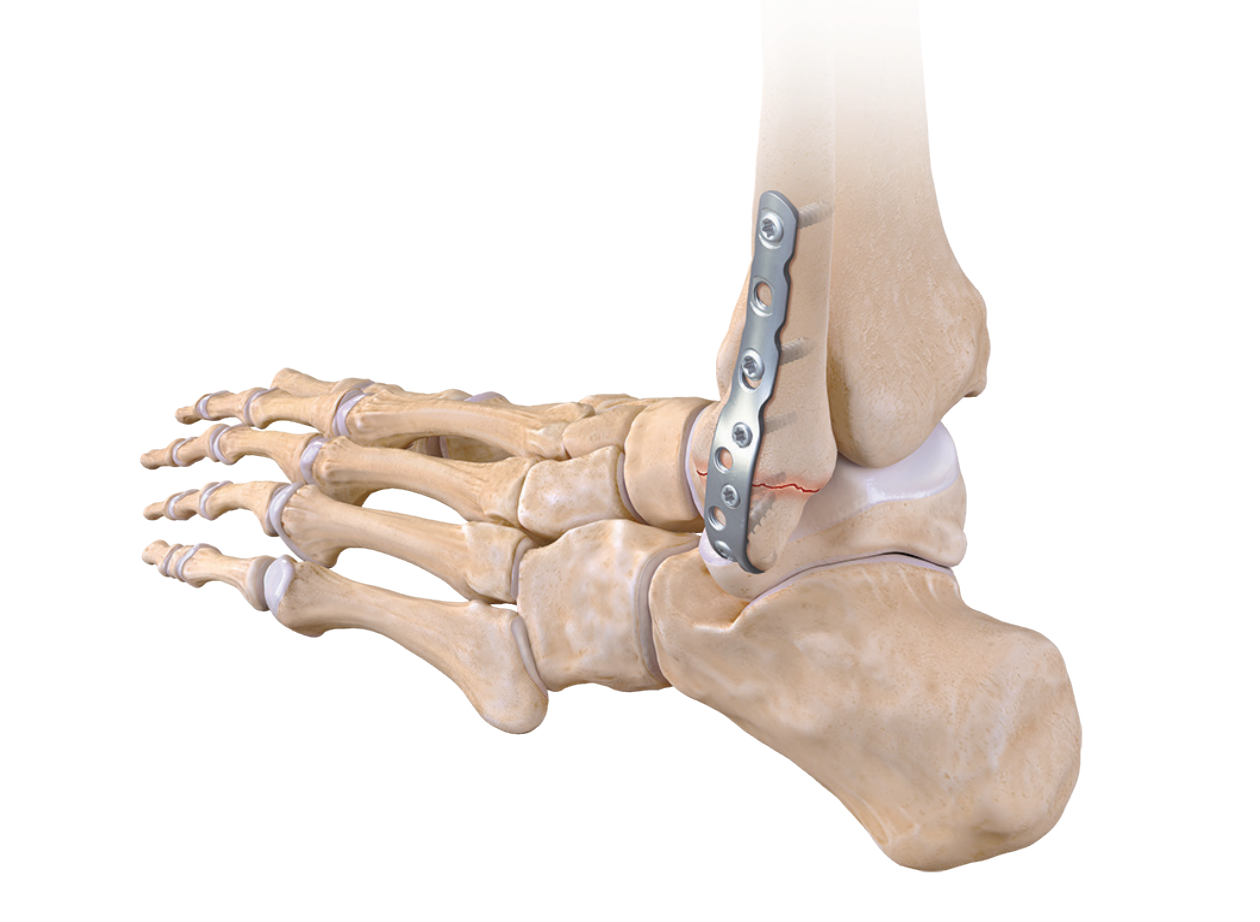

Ankle fractures can involve one or more bone segments. Some fractures, if stable or minimally displaced, can be treated non-surgically with a brace or cast. Displaced fractures or those involving multiple bone segments are more severe and require surgical intervention.

Stress fractures and non-displaced fractures typically do not require surgery and can be treated with a walker boot or cast. Severe fractures require reduction or surgical intervention.

Reduction: This involves realigning the fractured ankle and must be performed in the Emergency Room in cases of displaced fractures or ankle dislocations.